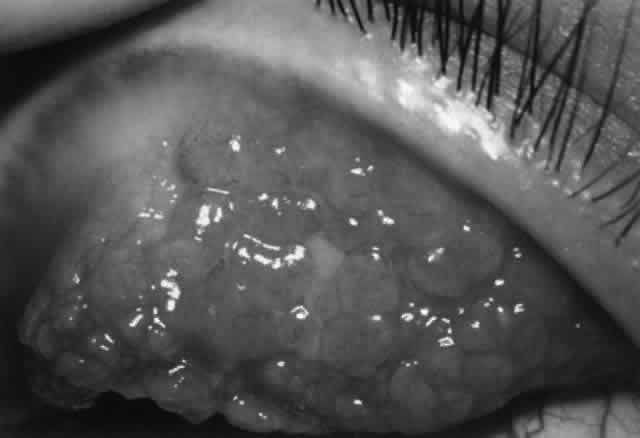

The Jones-Mote reaction is also known as cutaneous basophil hypersensitivity. It has been described as a unique form of type IV hypersensitivity in which there is a predominance of basophils. This form of hypersensitivity peaks at 24 hours, as opposed to contact and tuberculin reactions, which peak at 48 to 72 hours, and granulomatous reactions, which take 3 to 4 weeks to develop. It plays a role in vernal keratoconjunctivitis and contact lens-related giant papillary conjunctivitis (GPC).

There are approximately 50 million mast cells in the ocular and adnexal tissues of the human eye.31 In normal conditions, mast cells are concentrated in the substantia propria of the conjunctiva but are not found in the conjunctival epithelium. However, in disease states such as vernal and contact lens- induced giant papillary conjunctivitis (GPC), mast cells infiltrate the conjunctival epithelium. Each mast cell has as many as 500,000 receptors for IgE; IgE is bound to 10% of these receptors, thus coating the mast cell surface.7 The Fab portion of the IgE molecule extends from the mast cell surface, poised to bind antigen and thus trigger mast cell degranulation, resulting in type I immune reaction. There are two main types of mast cells in the conjunctiva, defined by their protease (tryptase and chymase) content. The T mast cell is tryptase positive and chymase negative, whereas the TC mast cell is tryptase positive and chymase positive. In the normal conjunctival substantia propria, both T and TC mast cells are present, with the latter being predominant. In inflammation (e.g., vernal, GPC), the TC mast cells greatly increase in number and also are found in the epithelium.32

2. Giant papillary conjunctivitis

1. Vernal keratoconjunctivitis

3. Contact lens/induced giant papillary conjunctivitis